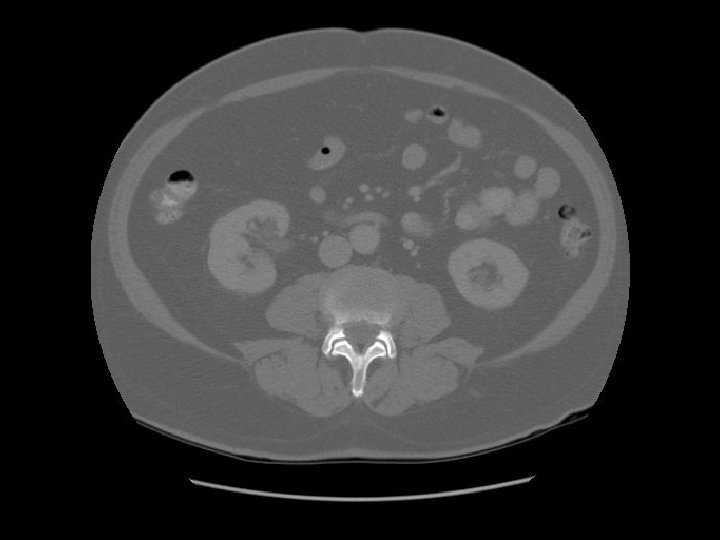

Kidney Right Kidney

Descending colon Right

Renal pelvis

Ascending colon Right colon with fecal material.